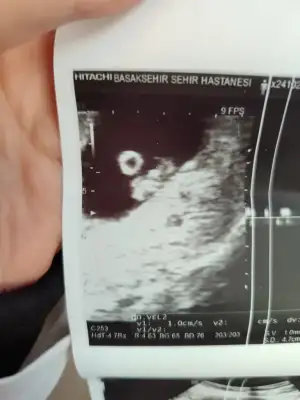

Gözünüz aydın :) karnınızdan mı duyuldu?6+4 keseyi ve kalp atışlarını gördüm Allah herkese bu duyguyu yaşatsın inşallah![]()

Kalp atışı düşük olsa söylerdi doktor canım icini ferah tutKizlar bugun tam 7 haftalik oldum, randevuden ciktim simdi devlete gittigim icin sadece gerekli kisa bir kac bisey soyledi, saglikli kalp atimi var 11. Haftada ikili teste cagirdi. Ama cihazdanmidir bilmem kalp atimi inanilmaz dusuk ve kalp gibide atmiyordu, doktora bagliyorum onemsemediginden bebegin tam kalbindeyken dnlemedi sanirm. Buda usg kagidim, darisi kalp atimi bekleyenlere ins![]()

Kac cm olduğu önemli mi ki benim doktorum gayet yolunda her sey sağlıklı dedi fotolarını verdi benimki vajinal ultrason olduğu için çok net baya olusmus öyle görünce bi garip oldum ben deBurda olcumleri yaziyormu kac cm oldugu